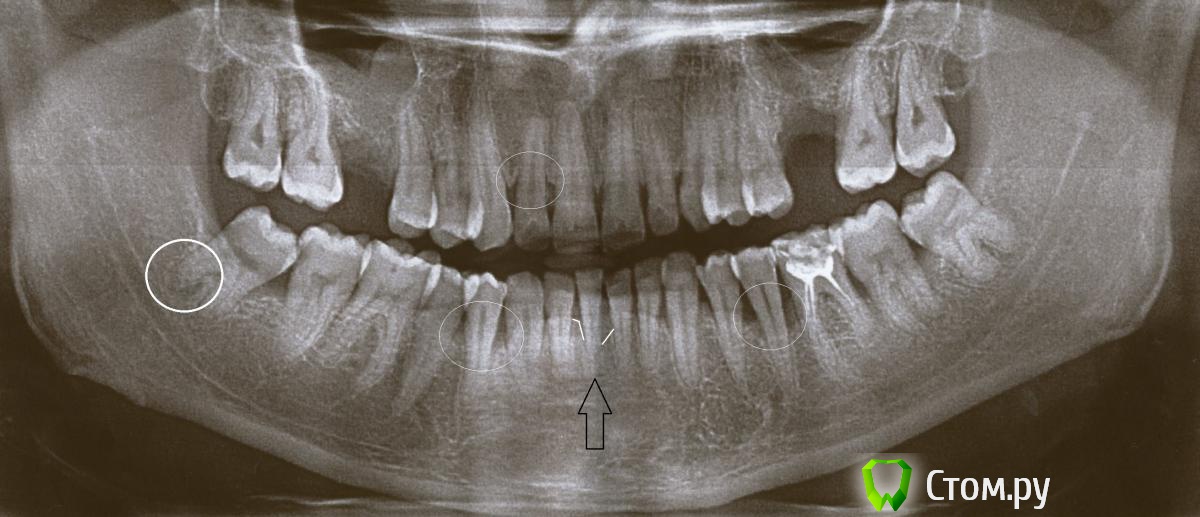

Алексей Александрович Опубликовано 11 апреля, 2014 Автор Поделиться Опубликовано 11 апреля, 2014 Вот мне ответил профессионал. Можете чо-нибудь добавить или наоборот раскритиковать?Добрый день.Характер резорбции костной ткани говорил о воспалительной причине, т.е. это пародонтИТ.И, кстати, нижний зуб слева на снимке - у него на верхушке корня есть небольшая киста, зуб требует депульпирования и лечения периодонтита.В прикрепленном файле ваш снимок с пометками:слева внизу указан зуб с периодонтитом (писал о нем выше). Остальные отметки показывают основные проблемные участки, где у зубов есть глубокие пародонтальные карманы. В области передних верхних зубов резорбция кости есть везде, но особенно в области 1 зуба. Внизу степень резорбции кости также неоднородна - преимущественно в области 4-5х зубов слева и справа.Самые большие изменения у зуба, о котором вы пишите (этот зуб отмечен черный стрелкой). Белые линии отмечают уровни до которых рассосалась кость.Нужен хороший пародонтолог. И тут нужно не только снимать качественно поддесневые зубные камни и проводить противовоспалительную терапию, но и нужно делать открытый кюретаж с подсадкой синтетической костной ткани особенно в области нижних зубов (не всех, а некоторых групп зубов). А также срочно депульпировать нижний резец и шинировать его к нескольким соседним зубам стекловолокном).По вашим назначениям я уже вижу полный непрофессионализм врача. Депульпирование пародонтитных зубов делается в случаях, если атрофия костной ткани больше 1/2 длины корня, у вас у нижнего резца резорбция (атрофия) значительно больше. Кроме того, лазер будет только способствовать увеличению скорости резорбции кости, т.к. при таком лечении вся причинная инфекция как была так и останется на своих местах, только немного станет по-меньше. Лечебные инъекции - это судя по всему уколы Линкомицина... А вот это уже серьезно. Серьезный вред может нанести.Уколы антибиотиков должны быть только внутримышечно либо в таблетках."повязка для нагноившегося кармана" - такой же бред.Лечение должно было быть примерно таким (основные моменты):1. Снятие наиболее массивных зубных отложений в 1ое посещение, промывание карманов, обработка десны гелем. Назначение 10ти дневного курса антибиотикотерапии, антисептических полосканий, и противовоспалительного геля для обработки десны.Депульпирование нижнего резца (в канале оставить лекарство, зуб сразу пломбировать нельзя).2ое посещение - продолжение снятия зубных отложений (в том числе поддесневых), промывание карманов, обучение правильной гигиене полости рта. Промывание корневого канала нижнего резца, смена лекарста.Далее - через несколько дней, когда десна успокоится, уменьшится ее отек - полировка поверхности корней в пародонтальных карманах и коронок всех зубов. Пломбирование корневого канала нижнего резца. Далее пациент сам продолжает делать все назначения.Далее - после полного стихания воспаления (через 10-12 дней) решается вопрос о необходимости чистки пародонтальных карманов от грануляций, т.е. о необходимости Открытого кюретажа. У вас это происходит особенно в области 4-5х зубов внизу и боковом резце вверху.Шинирование нижнего резца обязательно, или вы его очень быстро потеряете. Кости очень мало, зуб не держит нормально жевательную нагрузку - мигом расшатается и выпадет иначе. Ссылка на комментарий